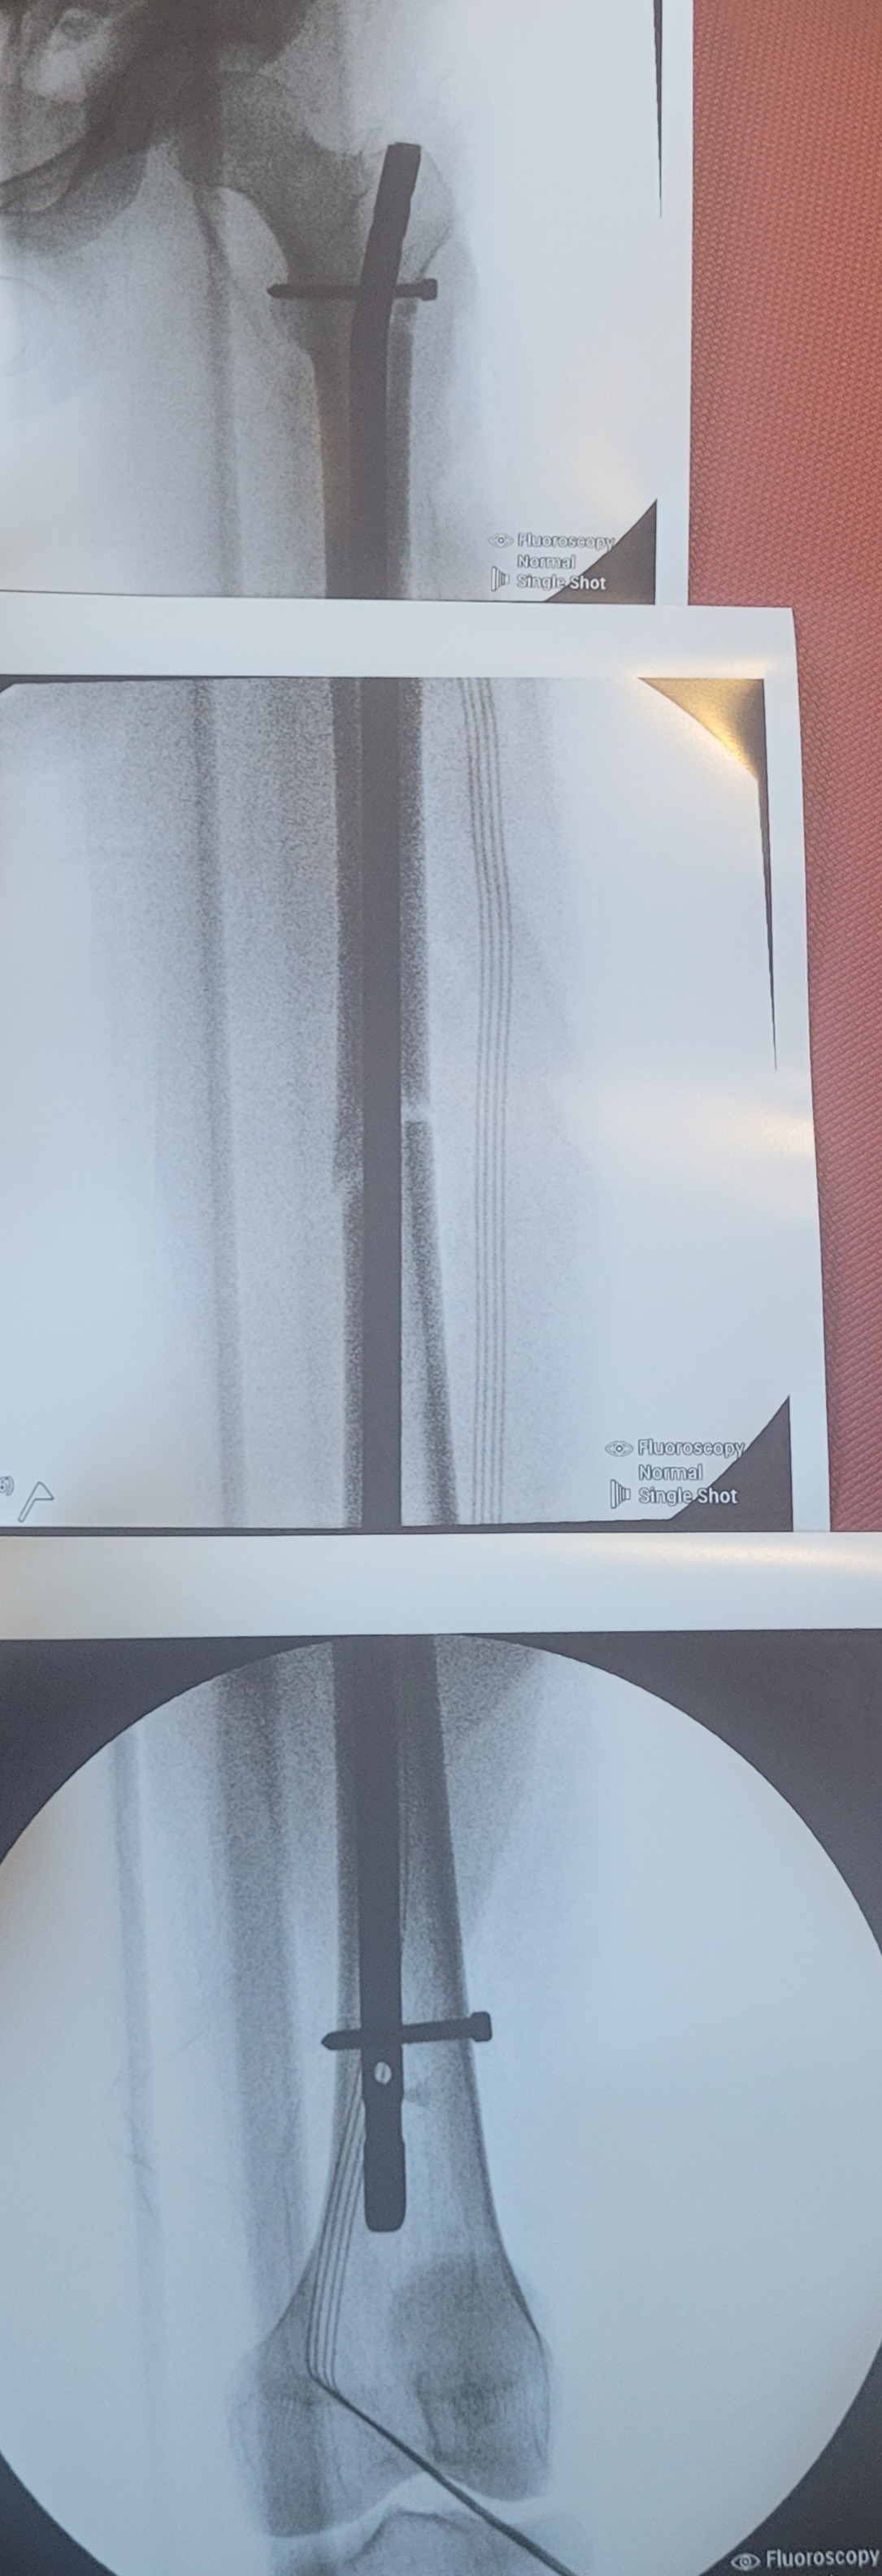

At the same time, her youngest daughter Amarissa was rushed by ambulance to Phoenix Children’s Hospital, where she underwent leg surgery to repair a broken femur. Doctors had to insert a metal rod to stabilize her leg. She remains separated from her mom as she recovers in the hospital.